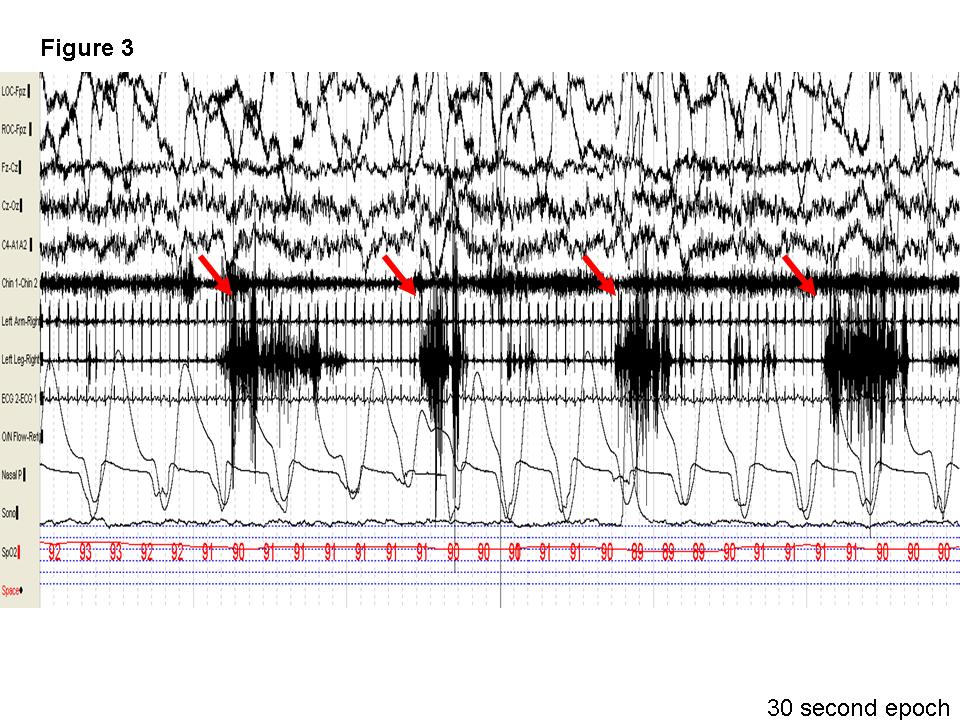

Discussion: Note the presence of recurrent right leg movements (left leg is covered by a sheet) in the first 10 seconds and the last 15 seconds of the video as the patient transitions from wake to stage N1 and in stage N1 respectively. Similarly, the 30-second epoch shows recurrent electromyographic (EMG) potentials at 1-2 Hz in the right leg with burst potentials greater than 250 milliseconds, lasting for longer than 10 seconds. This meets the criteria for hypnagogic foot tremors(1). Though alternating leg muscle activation (ALMA) is also a possible diagnosis, the surface EMG recorded activity (Figure 2) only from the right (indicated by the red box) and not from the left anterior tibialis muscle (highlighted by blue on figure 2). Of interest, periodic leg movements during wakefulness and not during sleep were also noted in our patient (Figure 3, red arrows).